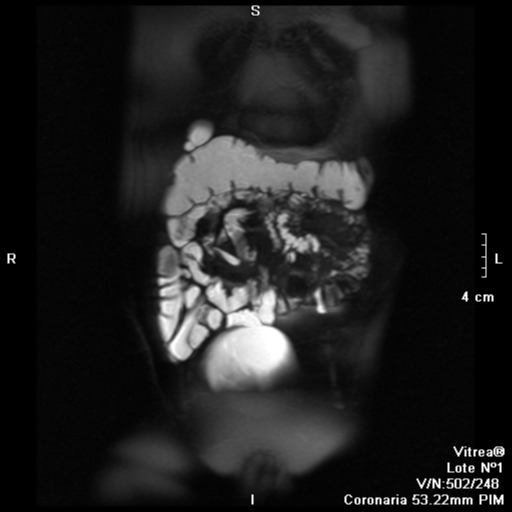

RM Pelvis

Prueba diagnóstica no invasiva que consiste en la obtención de imágenes de alta definición anatómica de la pelvis mediante el empleo de un campo electromagnético y ondas de radio (con un emisor y un receptor). No utiliza radiación ionizante. Se realiza para estudiar patologías del útero, del ovario, de las trompas y la vagina, ya sean de origen tumoral, inflamatorio o vascular. Esta prueba permite valorar órganos como la vejiga urinaria, la unión entre los uréteres y la vejiga, la próstata, las vesículas seminales, la uretra, los huesos de la pelvis, etc A veces requiere el uso de contraste intravenoso (Gadolinio) para caracterizar las lesiones.